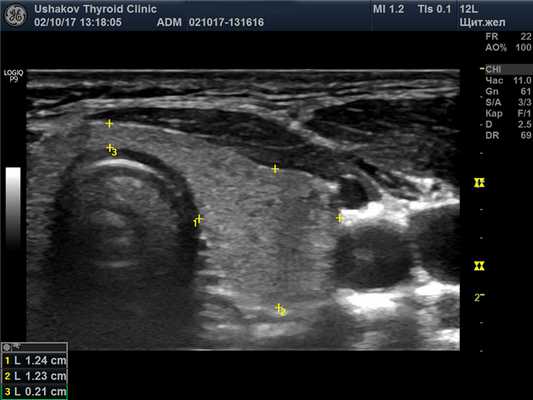

В правой доле щитовидной железы в центрально-каудальной части почти до её краев (в поперечной проекции) расположен овоидоподобной формы узел 22,9х20,7х33,1 мм (7,4 мл), окруженный по всему периметру чёткой гипоэхогенной границей-контуром, значительно неоднородный за счет множественных анэхогенных (жидкостных) участков (около 70% от объёма узла), преимущественно с чёткими границами в виде узких перегородок с изо- и гиперэхогенной (фиброзной) тканью и изоэхогенной тканью по периметру узла; при ЭДК заметно примыкание к узлу с кранио- и каудальной сторон магистральных сосудов, и умеренный кровоток по части периметра и мало интенсивный внутри узла (в перегородках); при эластографии SR 2,8 (3,3 - в обл. некоторых перегородок). Вне узла ткань изоэхогенная, почти однородная; в краниальном полюсе 21,2х15х15,1 мм (2,3 мл), а также медиально. В режиме ЦДК и ЭДК кровообращение в этой ткани в малой степени усилено.

Внеузловая ткань. У пациентки внеузловая ткань железы выглядит почти абсолютно нормальной, гормонообразующей. Эта ткань занимает всю левую долю, за исключением двух малых узлов, объём которых так мал, что им можно пренебречь (рис. 27.1-27.4).

Рис. 27.1. Пример 1. (левая доля, поперечная проекция).

Ткань доли и перешейка изоэхогенная, почти однородная. Граница железы чёткая.

Рис. 27.5. Пример 1. (правая доля, поперечная проекция).

Латерально и вентрально за узлом – лишь тонкий слой ткани. Медиально заметна значимая часть внеузловой ткани. Узел в поперечной проекции подобен кругу. Чёткий гипоэхогенный контур по всему периметру узла.